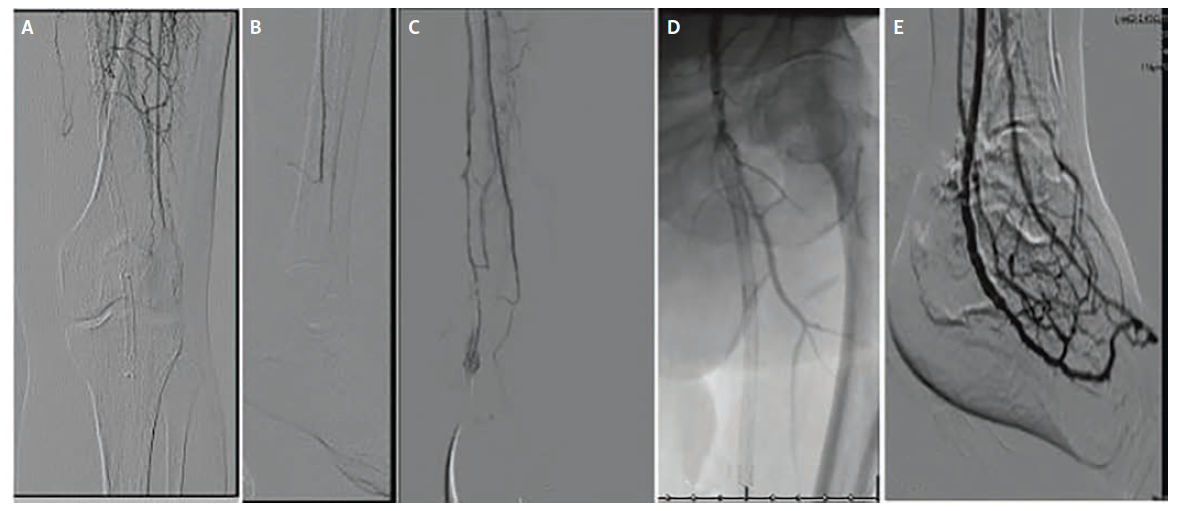

The third patient, a 72-year-old man (Figure 3), presented with Rutherford class IIa ALI manifested by a cold, painful foot and absent pedal signals. Imaging demonstrated thrombosis of a prior popliteal artery aneurysm stent graft with 3-vessel tibial runoff to the ankle but no pedal perfusion.

Initial management consisted of catheter-directed overnight thrombolysis aimed at restoring tibial flow. Given sluggish inflow, endovascular optimization was also performed with stent-graft relining of the superficial femoral and popliteal arteries and angioplasty of the tibioperoneal trunk and peroneal artery. Despite these maneuvers, there was no restoration of flow into the foot.

As no suitable distal arterial target was identified, the decision was made to proceed with PTA-based DVA. Using an arterial-venous crossing technique, the PTA was connected to the posterior tibial vein, and Viabahn covered stent grafts (11 mm x 100 mm, 13 mm x 100 mm, and 13 mm x 5 mm in overlapping fashion) were deployed to establish an arterialized venous outflow tract. Completion angiography demonstrated brisk hindfoot venous flow but only partial opacification of the plantar pedal venous loop.

At 1-month follow-up, additional pedal venous arch angioplasty was performed, which improved venous loop filling and forefoot perfusion. Ultimately, the patient required an anticipated TMA 26 days post-DVA, but major amputation was avoided and durable limb perfusion was maintained through the venous circuit.

At 6-month follow-up, Doppler ultrasound demonstrated excellent flow to the foot with sustained patency of the DVA, confirming durable revascularization and long-term effectiveness of the venous arterialization strategy.